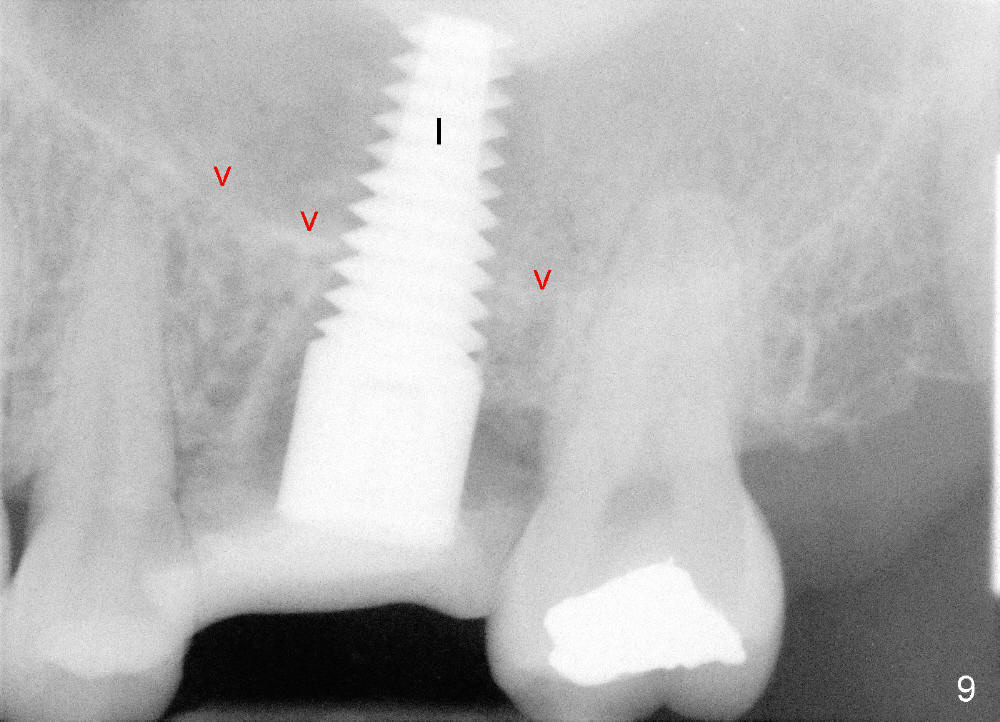

让我们再举例说明证明上颌窦中有骨质:三个月前,四十来岁女士来诊所诊治,左上六不适(图六),咬合面有一个大块银汞充填,周围有裂纹,去除银汞充填后,裂纹延伸至髓腔顶(图七),好像不到髓底,所以尝试根管治疗,但是疼痛没有消失,我们临时决定拔牙立即植牙,但是当时没有足够时间注意上颌窦底板,两眼直盯鄂侧根尖(图六:P),因此最后植牙就植入那么深(图九:I),晚上欣赏自己“杰作”时,才发现上颌窦底板(箭头),虚汗一身:一大节植牙捅进上颌窦,马上打电话给病人,她有些鼻血,但是她还不愿意回来复诊。拔牙后准备在中隔正中植牙,使用骨凿,tap形成植牙窝,后者颊侧骨壁有小面积穿孔,但是上颌窦膜还完整,最后植牙掉入鄂侧牙槽窝(图八;S:中隔;MB:近中颊侧牙槽窝;DB:远中颊侧牙槽窝),植牙很牢,torque>60Ncm。